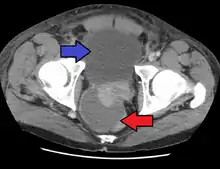

Abscess of the prostate (red arrow) resulting in urinary retention (blue arrow)